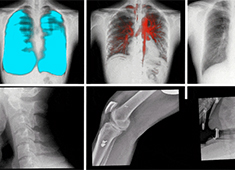

三维重建技术在医学影像诊断中的应用价值

三维重建技术在医学影像诊断中的应用非常广泛,主要包括以下几个方面:1.诊断疾病:通过三维重建技术,医生可以更直观、清晰地观察到患者体内的异常情况,如肿瘤、骨折等,从而更准确地诊断疾病。...